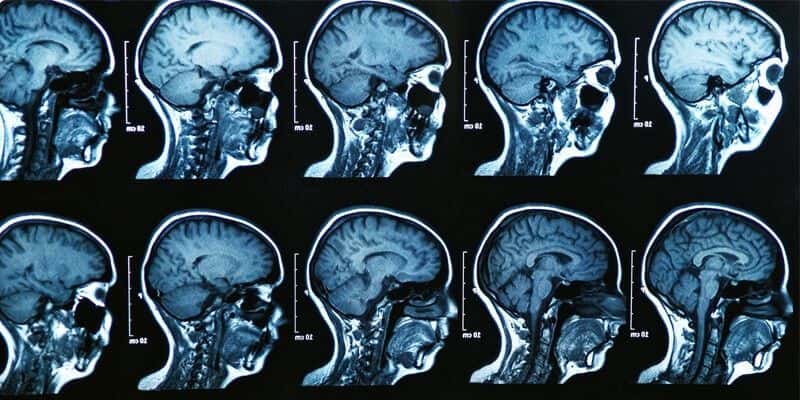

Delayed MRI Allegedly Leads To Patient’s Rapid Neurological Decline

This case involves an 80-year-old male with a history of hypertension and paroxysmal atrial fibrillation. He had been off of the blood thinner Warfarin for several months when he presented to the emergency room with altered mental status. On initial exam, he was difficult to arouse with slurred speech and an expressive aphasia. A head CT was performed which did not reveal any acute intracranial abnormality. The primary differential diagnosis was an acute cerebrovascular accident due to the patient’s history of atrial fibrillation combined with his onset of neurologic deficits. A stat brain MRI was ordered but was not completed until the following day. In the meantime, the patient was admitted to the internal medicine service. Imaging revealed an acute infarct in the posterior temporal and occipital regions, bilateral cerebral peduncle infarcts, and a blot clot at the basilar terminus obstructing flow to the superior cerebellar arteries. The patient’s neurologic status continued to rapidly decline and he eventually succumbed to his injuries.